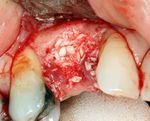

في الحالات التي تكون فيها انسجة عظم الفك غير مناسبة لتقبل الغرسات، يجب القيام بعلاجات مسبقة لعدة اشهر قبل زراعة الاسنان لانشاء منطقة مناسبة في الانسجة لتلقي الغرس (تركيب العظام).

اذا كان العظم على استعداد لتلقي الزرع (أحيانا بعد سلسلة علاجات مسبقة)، يمكن البدء بعملية زرع الاسنان. يتم تثبيت المسامير المعدنية اللولبيه براغي، بعظم الفك. في سلسلة اخرى من العلاجات بعد فترة من ادخال البراغي، تبدا عمليات اعادة البناء عن طريق أخذ القياسات وانشاء التاج/الجسر. عندما يدور الحديث عن فترة الانتظار بين تركيب الغرسات وبين تنفيذ الاستبناء النهائي، فان هنالك اكثر من نهج واحد. النهج المتبع غالبا هو الانتظار لمدة 6 أسابيع على الأقل حتى تلتئم الانسجة، وأحيانا تصل فترة الانتظار لعدة شهور.